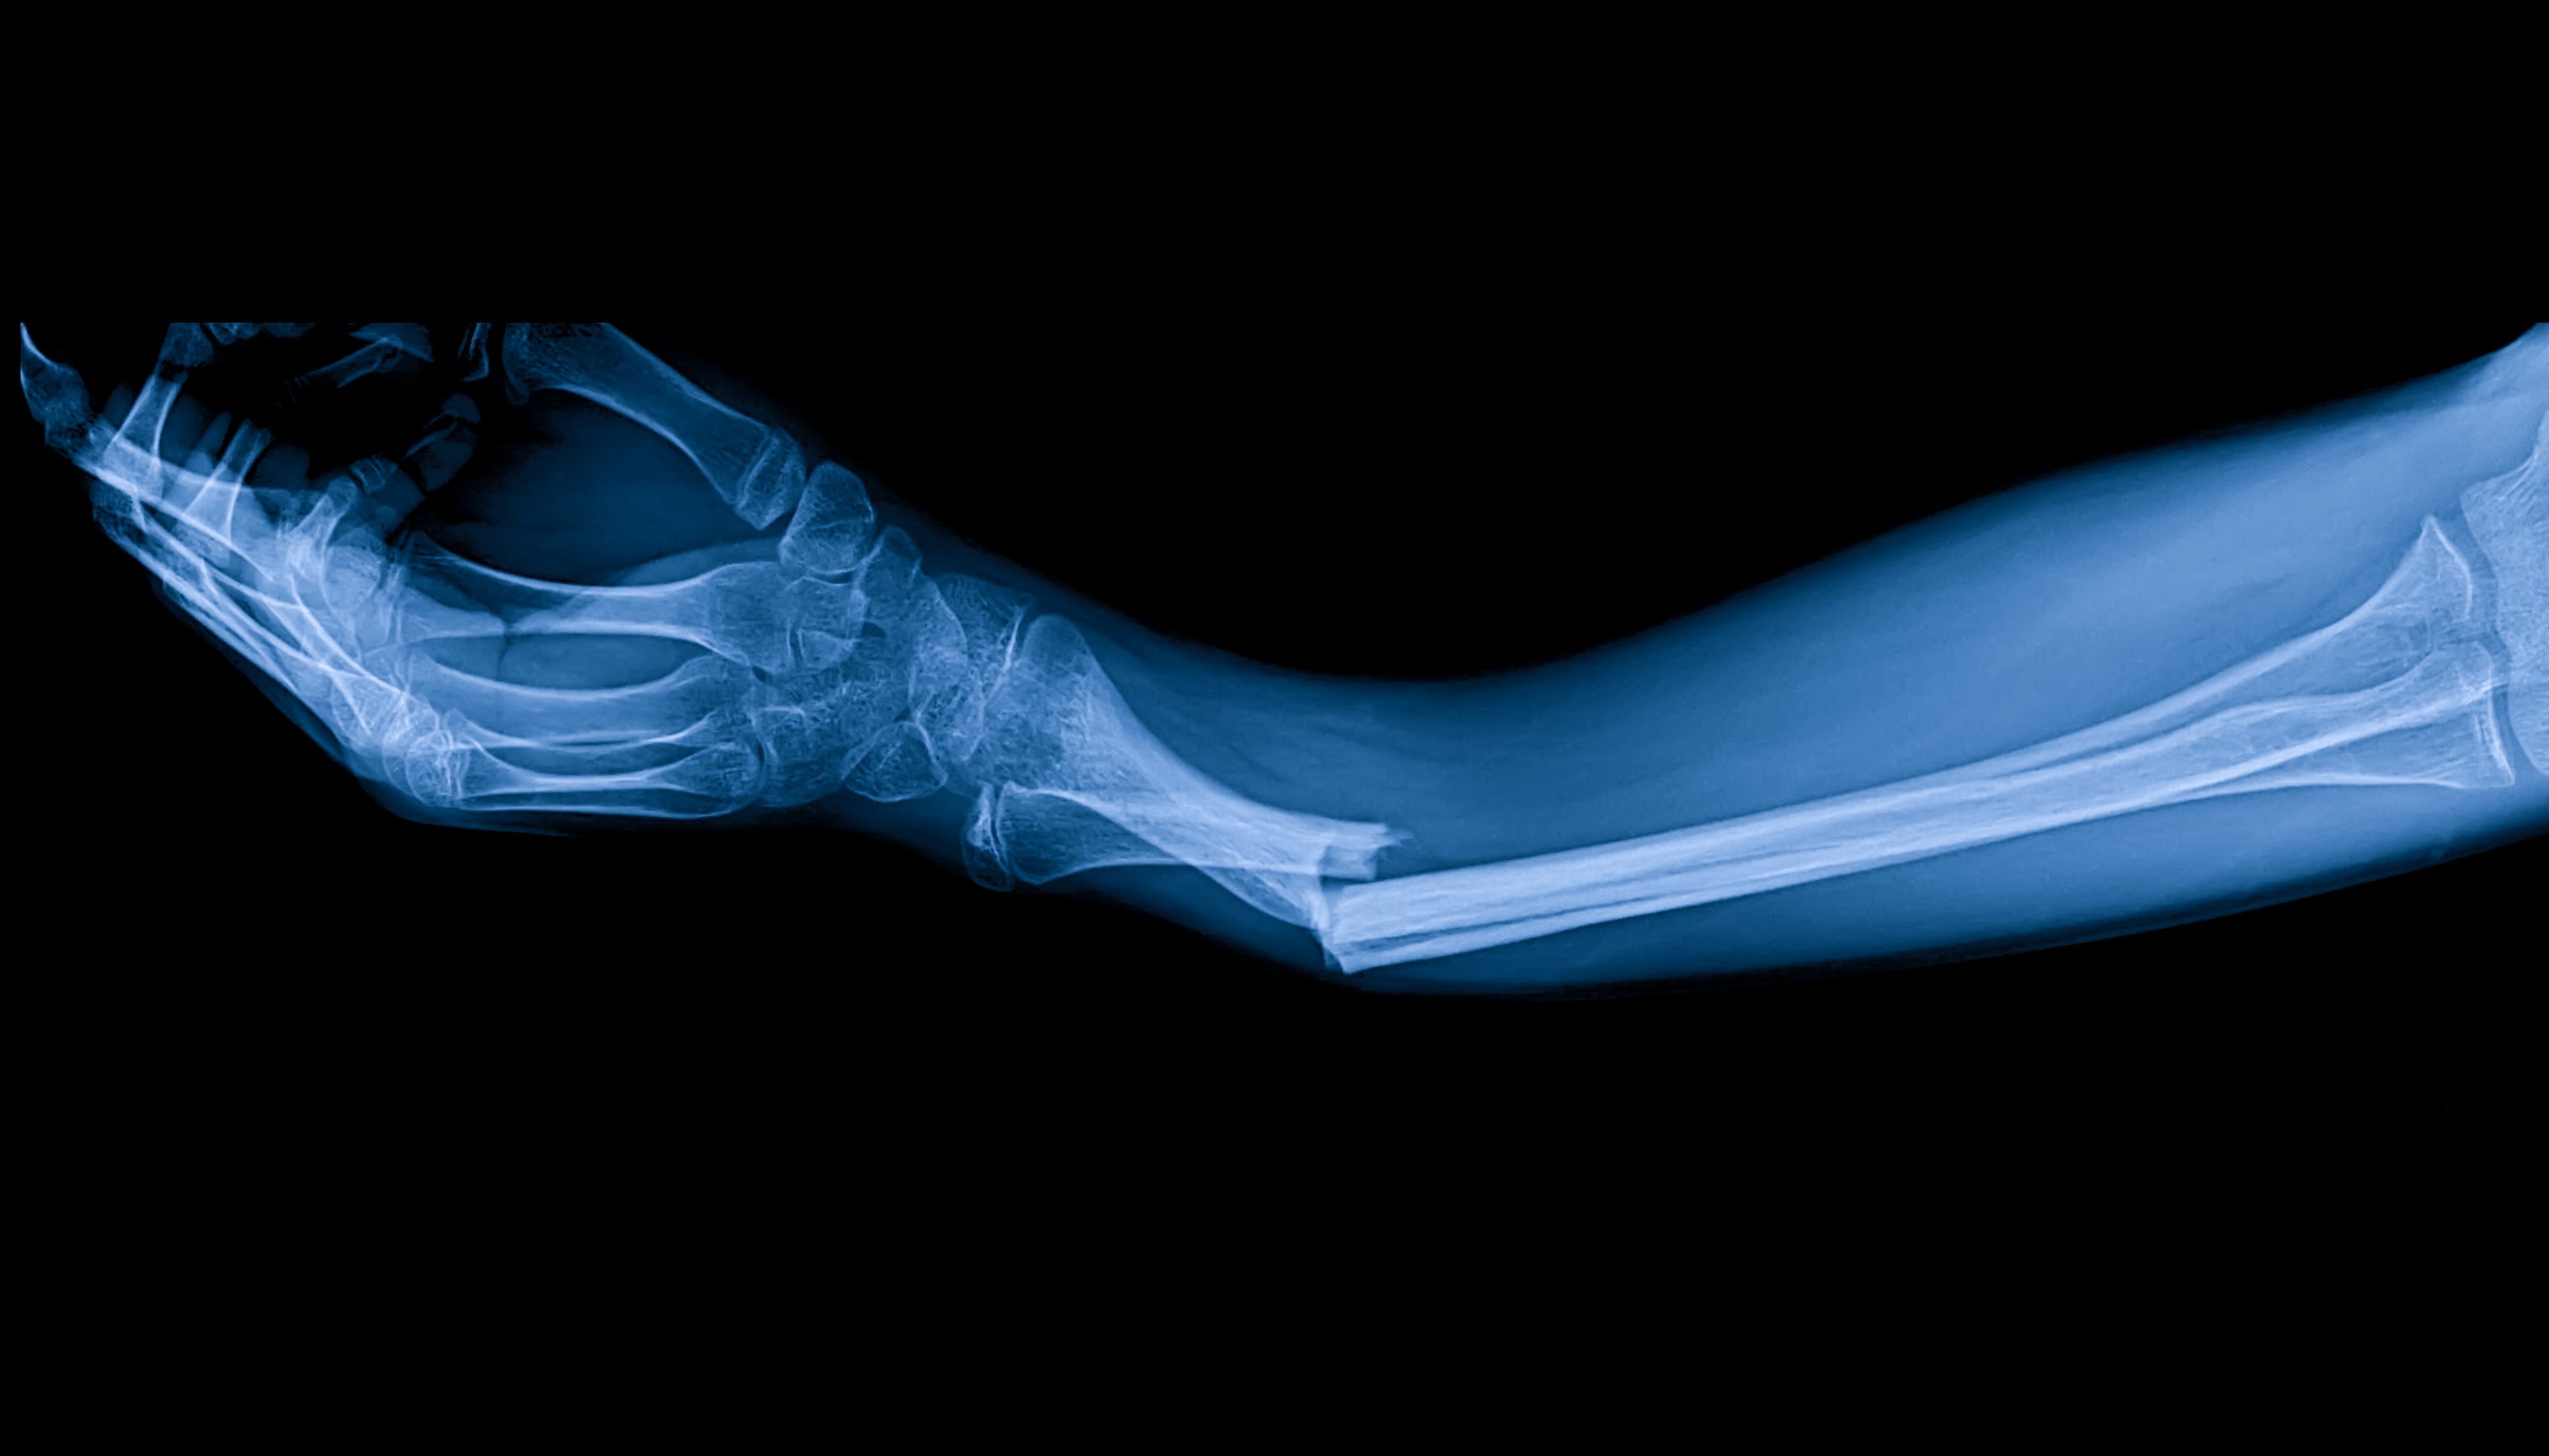

Las fracturas óseas pueden ser consecuencia de accidentes, caídas o lesiones deportivas, y requieren un periodo de recuperación importante que varía en función de la gravedad y la localización de la fractura. Los métodos tradicionales de curación ósea incluyen la inmovilización con yesos o férulas y, en ocasiones, intervenciones quirúrgicas. La terapia PEMF complementa estos métodos estimulando la reparación celular y el crecimiento óseo a nivel molecular.